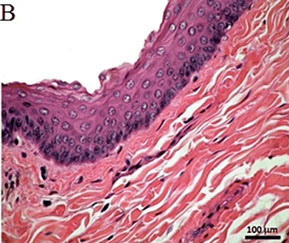

Histology

Parotid gland

Serous salivary gland, serous acini, zymogen granules, intercalated ducts, striated ducts, interlobular ducts c stratified epithelium, lobules c connective tissue septa and nearby LN c capsule